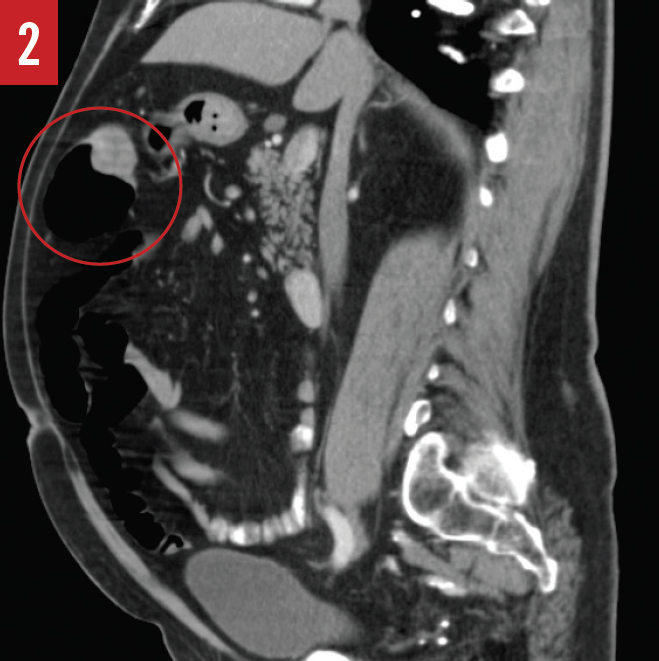

During the hemicolectomy, when the ascending colon was mobilized and palpated, the tattooing done during the colonoscopy had faded and was no longer visible due to the prolonged time between the colonoscopy and the hemicolectomy. The ascending colon was then palpated, and a firm, rubbery mass was felt within the cecum as described by CT. The ascending colon from the terminal ileum to the border of the liver was then excised and examined; however, no tumor was present within the cecum or the ascending colon, only a fatty infiltrate near the ileocecal valve. The surgeon then reviewed the CT scan and report to identify the cecal mass, at which time a mass was also noted in the hepatic flexure (Figures 2-4).

Confused by the conflicting information, the surgeon then palpated the remaining colon and felt a mass within the hepatic flexure. The hepatic flexure was then excised, and the mass was examined histologically and found to be a tubulovillous adenoma with high-grade dysplasia. It became apparent that the original mass that had been visualized on colonoscopy and that had been thought to be located in the cecum was in fact in the hepatic flexure, and during the extended time between colonoscopy and hemicolectomy, the mass had progressed from low-grade dysplasia to high-grade dysplasia.

In the example case presented here, the surgeon visualized a mass in the hepatic flexure that he perceived to be in the cecum. The CT imaging and radiology report corroborated this finding, stating that there was a cecal mass but with no mention of a mass in the hepatic flexure or in the rectosigmoid junction. Nevertheless, on second look, the hepatic flexure mass was apparent on images in all 3 viewing planes, and the rectosigmoid junction showed wall thickening that should have been flagged as abnormal for further workup, as well.